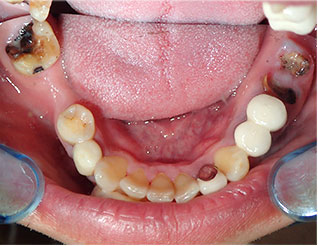

[スタンダードジルコニア16本] - この方は全体的に虫歯や欠損が多く、抜歯が必要な部分もありました。